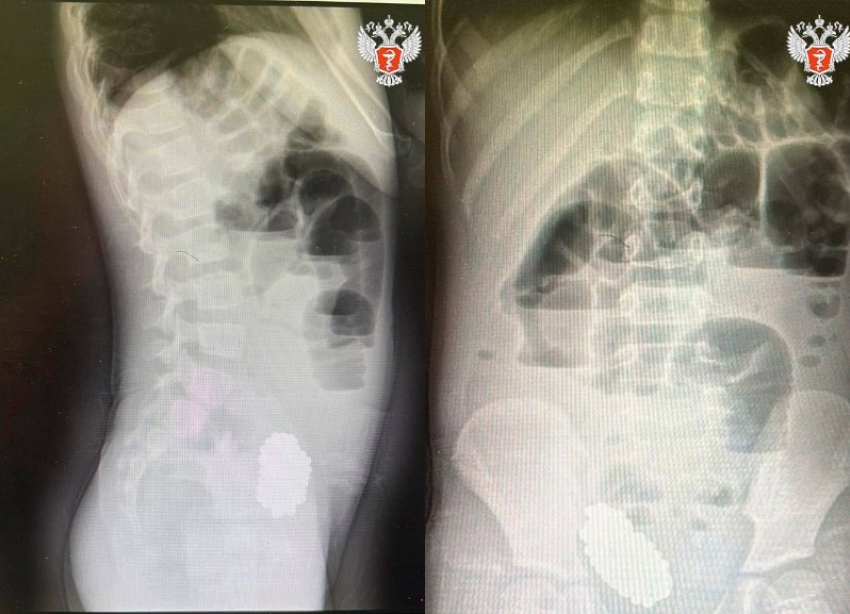

При обследовании выяснилось, что причина страданий кроется в кишечной непроходимости. Виновником оказались 134 магнитных шарика. Малышка проглотила их, и они, соединившись, образовали плотный ком, который сдавил кишечник.

Родители были в шоке: девочка ни разу не жаловалась на то, что что-то проглотила. Лишь после рентгена они вспомнили о пропавшей игрушке с магнитами, принадлежавшей старшему брату.